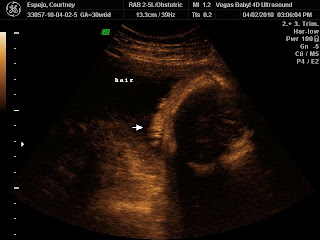

She is already sporting some major hair. They said she should be born with a full head of it!